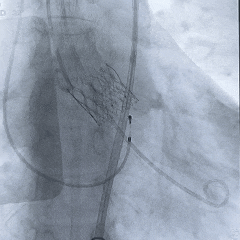

术中影像

根部造影:中大量反流,瓣叶活动度差

20mm球囊预扩:

轻微腰,无漏,左冠灌注正常

瓣膜0位初始定位

瓣膜稳定释放至全展开

工作位造影:无冠窦侧瓣下2mm左右,瓣膜形态直筒

左冠切线位,可见左冠开口无遮挡

多角度观察,确认瓣膜稳定

脱钩后造影,瓣膜位置可,几乎无瓣周漏

左冠切线造影,确认冠脉无遮挡

外周血管造影无损伤,手术结束